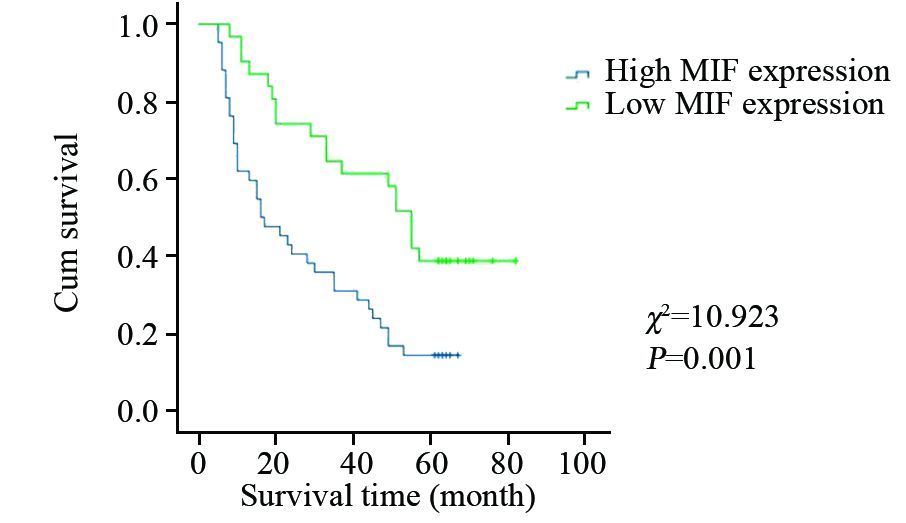

结果MIF在贲门癌组织中高表达42例,高表达率为57.5%。MIF表达水平与患者的年龄、性别、肿瘤分化程度、淋巴结转移和TNM分期无关(P>0.05),与肿瘤的浸润深度有关(P=0.025)。MIF高表达组和低表达组的生存期用Kaplan-Meier方法评估,并用Log rank检验进行比较,两组之间生存率差异有统计学意义(P=0.001)。多因素Cox回归模型分析表明,淋巴结转移(P=0.025)、MIF表达水平(P=0.001)是影响贲门癌预后的独立危险因素。

ResultsThe high MIF expression rate was 57.5%. There was no significant correlation between the levels of MIF expression and age, gender, tumor differentiation, lymph node metastasis, TNM stages(P>0.05). However, the high MIF expression was strongly correlated with the depth of invasion(P=0.025). The survival rates were significantly different between the two groups(P=0.001). The multivariate Cox regression model analysis showed that lymph node metastasis(P=0.025) and the levels of MIF expression(P=0.001) were the independent prognostic risk factors for cardiac carcinoma.